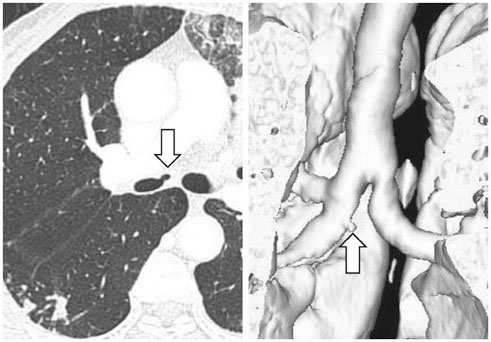

We identified two main types of ACB: blind-end (51.7%) and lobule (48.3%). The blind-end ACB was further classified into three subtypes: blunt (70%), pointy (23.3%) and saccular (6.7%). The lobule ACB was also further classified into three subtypes: complete (46.4%), incomplete (28.6%) and rudimentary (25%). Division location to the upper half bronchus intermedius (79.3%) and medial direction (60.3%) were the most common in all patients. The difference in division direction was statistically significant between the blind-end and lobule types (p = 0.019). Peribronchial soft tissue was found in five cases. One calcification case was identified in the lobule type. During follow-up, ACB had disappeared in two cases of the blind-end type and in one case of the rudimentary subtype.

The proposed classification of ACB based on imaging, and the follow-up CT, helped us to understand the various imaging features of ACB.